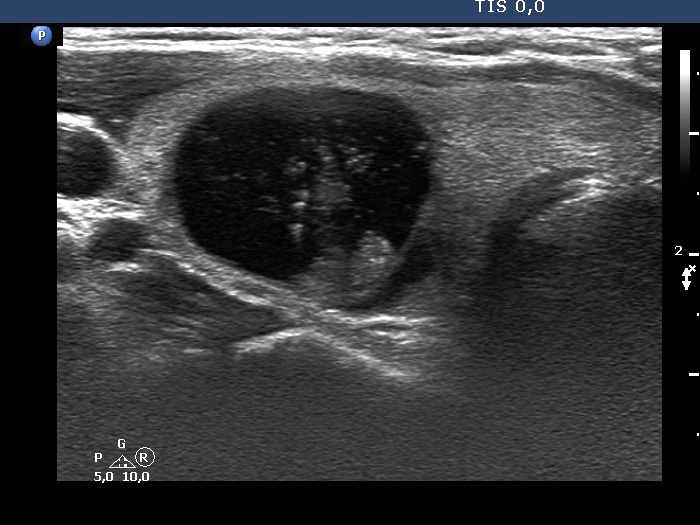

Examination 3 years later (ultrasonographic picture 3)

Right lobe, longitudinal scan

Right lobe, another transverse scan. The solid part presents non-specific granulations.